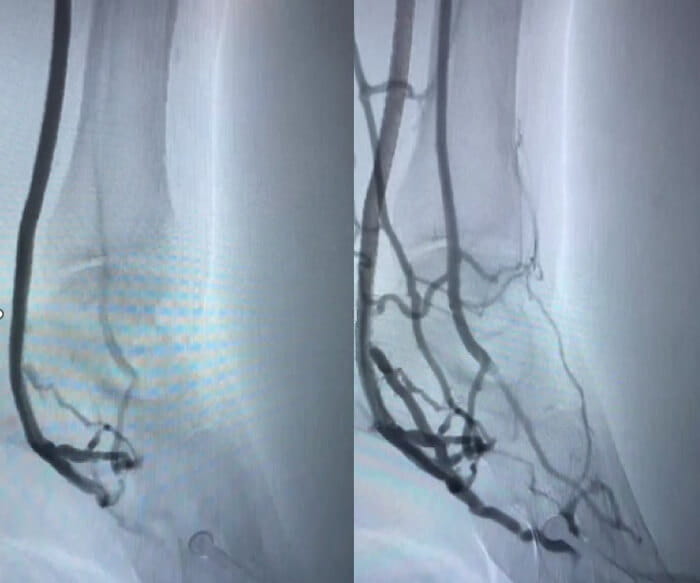

LimFlow crossing stent imageLimFlow crossing stent.

LimFlow scan before and afterScans of patient before and after LimFlow.